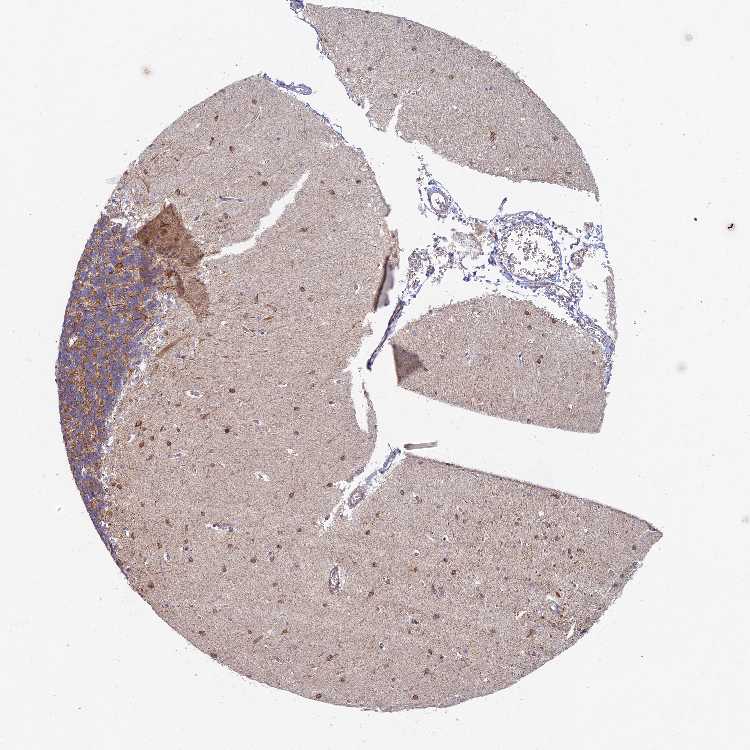

CEREBELLUM - Antibody stainingi

Antibody staining in the annotated cell types in the current human tissue is reported as not detected, low, medium, or high, based on conventional immunohistochemistry profiling in selected tissues. This score is based on the combination of the staining intensity and fraction of stained cells.

Each image is clickable and will lead to virtual microscopy that enables deeper exploration of all samples and also displays staining intensity scores, fraction scores and subcellular localization as well as patient and tissue information for each sample.

Antibody HPA043807

Purkinje cells Low

Cells in granular layer Medium

Cells in molecular layer Medium